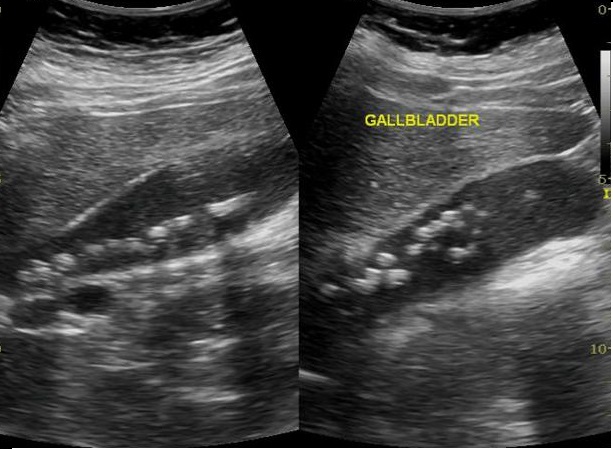

Image echographique de

multiple calcul vesiculaire avec epaissisement de la

paroi vesiculaire tres marquee . Cholecystite aigue

lithiasique |